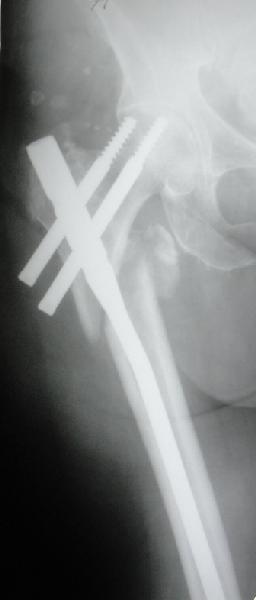

Фиксация * reversed obliquity* подвертельных переломов - дело непростое.

На мой взгляд, причиной телескопирования явилось несоответствие диаметра гамма нэйл с диаметром канала подвертельного отдела бедра: обратите внимание на величину протрузии шеечного винта и величину медиализации дистального фрагмента - они одинаковы, смещение или телескопирование фрагментов происходило до того момента, пока гамма нэйл не упёрся в медиальный кортекс и образовалось пространство между латеральным

кортексом и латеральной поверхностью гвоздя.

E> На мой взгляд, причиной телескопирования явилось несоответствие

E> диаметра гамма нэйл с диаметром канала подвертельного отдела бедра:

Диаметр гаммы в диафизарной части ~11 мм. А диаметр канала, тем более у пожилых с остеопорозом, может быть мм 15. Даже рассверливать обычно не приходится, после формирования широкого канала в вертельной области можно сразу толкать гвоздь, он влетает, как карандаш в стакан. Так что соответствия диаметров не бывает никогда. Однако представленная ситуация случается далеко не каждый раз. Если гвоздь в центральном отломке входит чуть медиальнее верхушки вертела, и идет вдоль передне-латеральной стенки центрального отломка, то все будет хорошо.

В приложении похожий пример, к счастью, пациентка появилась не после, а "за полчаса" до протрузии. Пересинтезировали с исправлением ошибок.